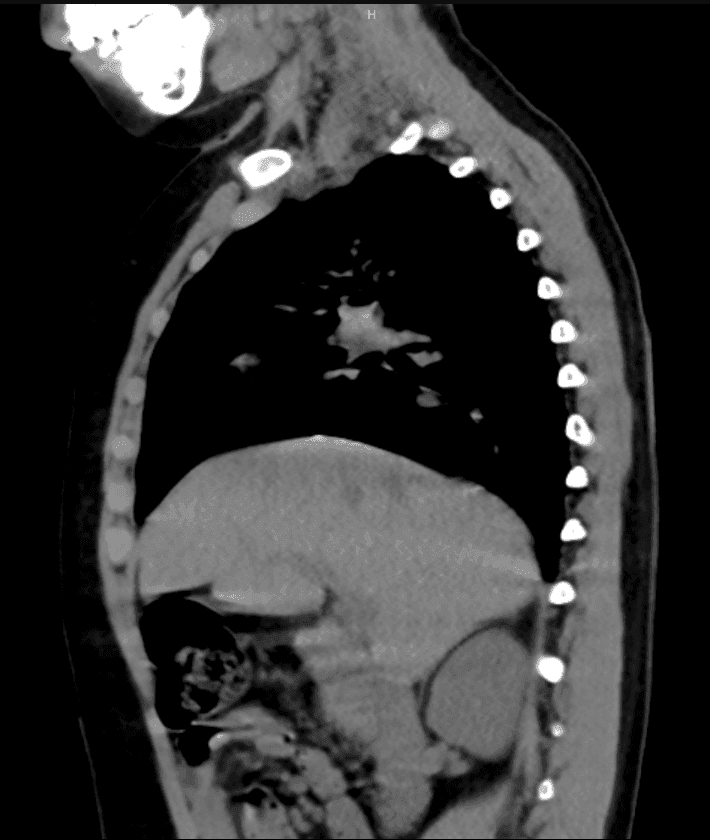

La Tomografía Axial Computada (TAC) es una de las herramientas más poderosas de la medicina moderna. En Grupo Imaginem, elevamos este estándar con equipos que integran Inteligencia Artificial para mejorar la nitidez de la imagen mientras reducen drásticamente la exposición a radiación.

Nuestra capacidad de realizar reconstrucciones tridimensionales permite a los médicos cirujanos planificar intervenciones con una precisión milimétrica, observando estructuras óseas y vasculares desde cualquier ángulo.